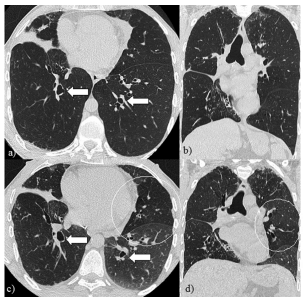

Los hallazgos tomográficos sugerentes de SBO

incluyen patrón en mosaico parcheado y difuso

más evidente en las adquisiciones en espiración

como expresión de atrapamiento aéreo, atelectasias

predominantemente subsegmentarias y marcadas

bronquiectasias que afectan la totalidad del parenquima pulmonar. Además, pueden reconocerse

opacidades en árbol en brote y peribronquiales

como signos de inflamación de la pequeña vía aérea que en caso de la variante reversible remiten

tras la administración de azitromicina3-5. Figura 1